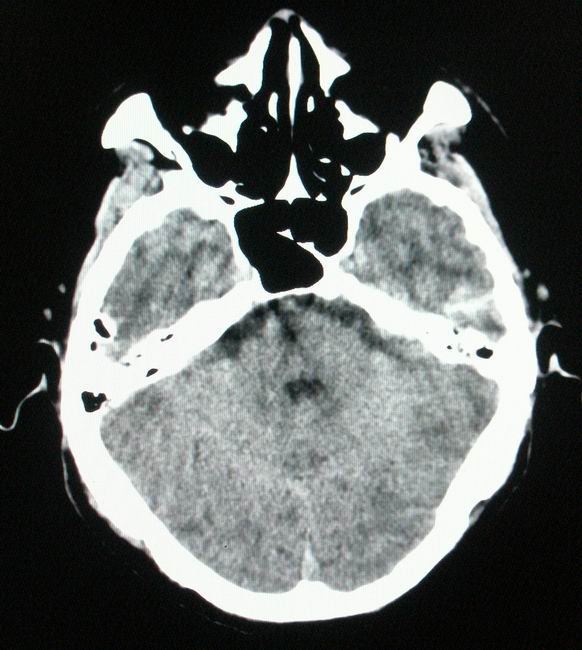

以下是引用随光逐影在2008-4-5 7:46:00的发言:[br]1)考虑为:多发性脑转移瘤。建议:行进一步检查。2)多发性腔隙性脑梗塞。3)脑白质病。4)脑萎缩。

以下是引用zjzjr在2008-4-5 9:00:00的发言:[br]1.双侧颞叶占位性病变,考虑为转移瘤可能性大。[br]2.左侧基底节区陈旧性腔隙性脑梗塞。[br]3.脑白质病。建议mri进一步检查。

以下是引用xuhuihong在2008-4-5 0:59:00的发言:[br]1.双侧颞叶占位性病变,考虑为转移瘤可能性大。[br]2.左侧基底节区陈旧性腔隙性脑梗塞。[br]3.脑白质病。建议mri进一步检查。

以下是引用形影不离在2008-4-4 23:29:00的发言:[br]1.双侧颞叶占位性病变,考虑为转移瘤可能性大。[br]2.左侧基底节区陈旧性腔隙性脑梗塞。[br]3.脑白质病。